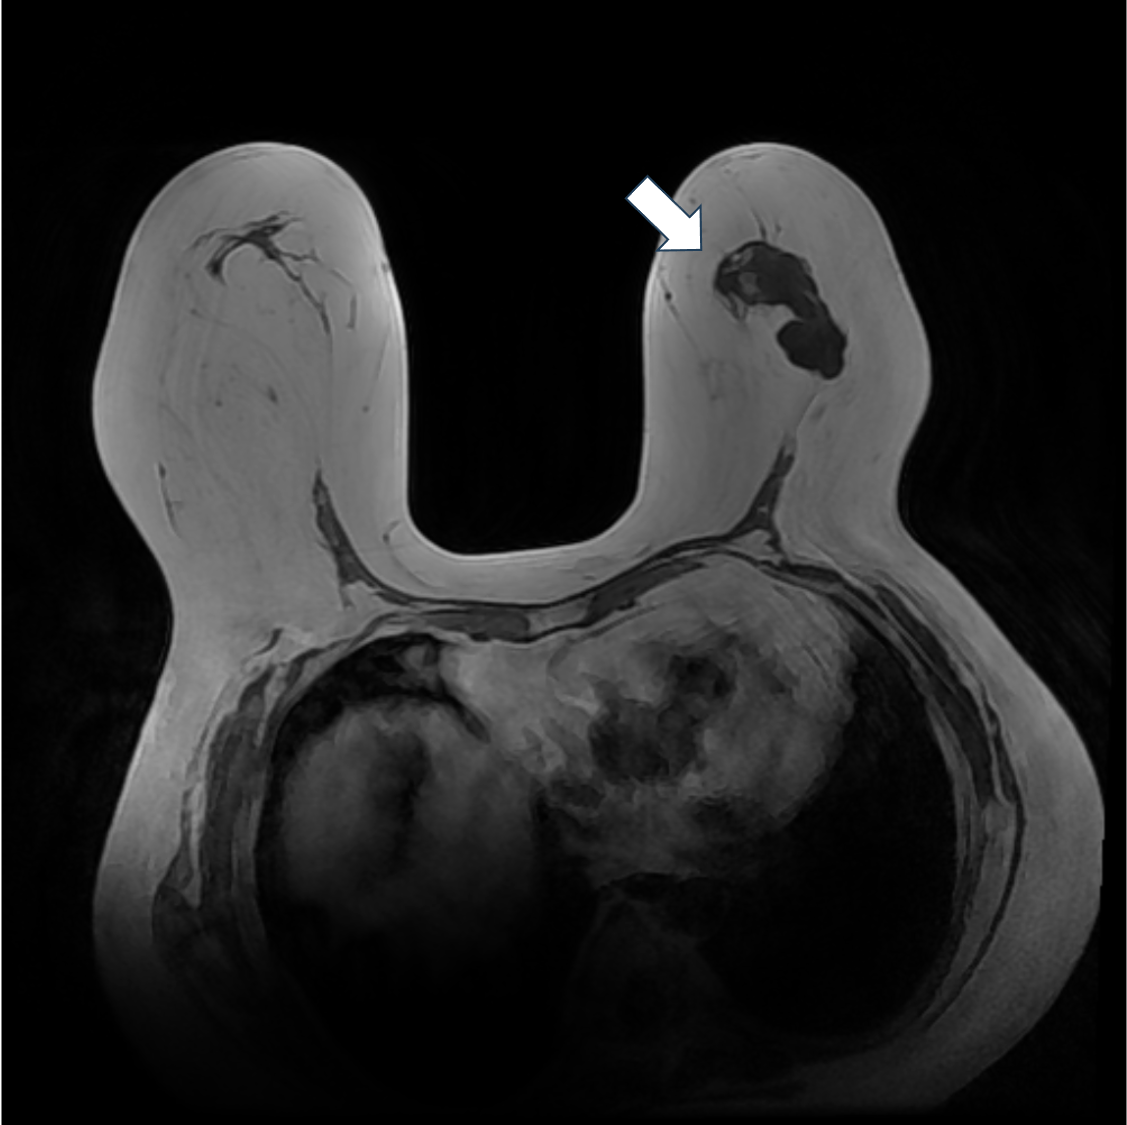

2. 脂肪抑制T2強調画像(造影前)

脂肪抑制T2強調像では腫瘤の乳頭側は軽度高信号を示すが、それ以外の部分は明瞭な高信号を示す。